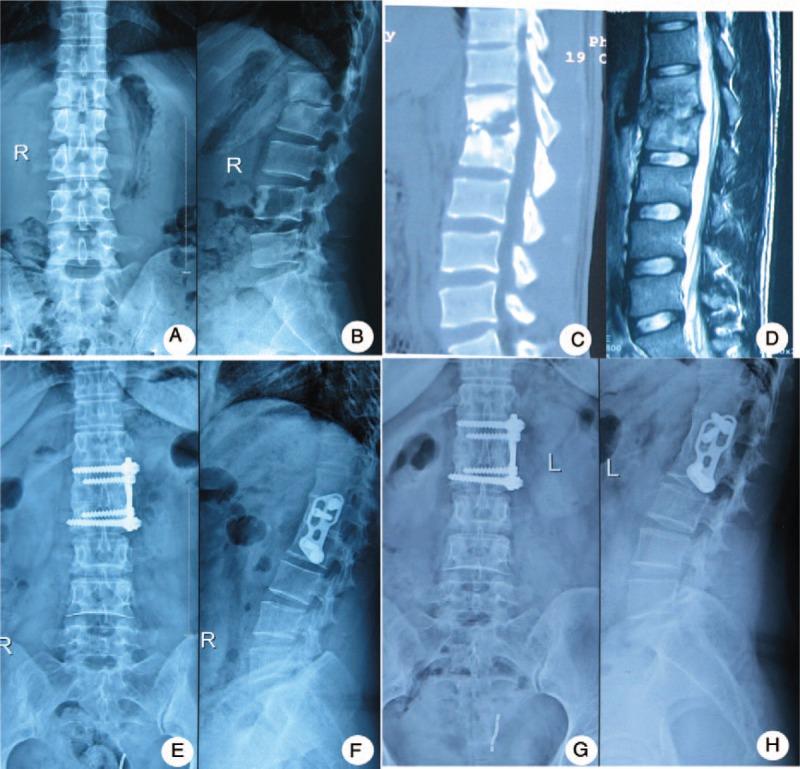

Surgical intervention is an important option for treating lumbar tuberculosis. Previous studies have reported different surgical intervention procedures. To our knowledge, few studies have compared the clinical results of mid-term follow-up of 3 different surgeries in surgical treatment of spinal tuberculosis. This study's purpose is to evaluate the effectiveness of 3 different surgeries for the treatment of lumbar tuberculosis in adult and analyze the mid-term influence of the surgery on quality of life.Between June 2004 and January 2010, a total of 137 adult patients (54 women and 83 men) with lumbar tuberculosis were recruited for this study. The patients were divided into 3 groups based on administered surgeries: posterior, anterior, and combined posterior-anterior. The trauma index (operation time, blood loss, length of hospital stay, and complications), imaging parameters (segment kyphotic angle, correction rate, loss angle, and bone fusion time), and quality-of-life indicators, including Oswestry Disability Index (ODI), the Frankel grade, visual analog scale (VAS), and Macnab score, were collected.The posterior group experienced the lowest trauma index, whereas the combined group faced the highest trauma index. The anterior group's kyphosis correction rate of (52% ± 5.45%) was significantly inferior to the posterior group (74% ± 5.04%) and the combined group (69% ± 7.95%), whereas the loss of correction in the anterior group (2.5°) was higher than the losses of correction in the posterior group (0.8°) and combined group (1.1°). The mean bone fusion times of the 3 groups were similar. Postsurgery quality of life was markedly improved in all patients. The improvement rates of the ODI, VAS, and the excellent and good rate per the Macnab score were similar among the 3 groups at the final follow-up.Based on a retrospective study, for patients with lumbar tuberculosis, use of the anterior approach should be limited. Although the combined approach produced satisfactory outcomes, it remains more traumatic. Compared with the anterior surgery and the combined surgery, the posterior-only approach is safer and less invasive.

手术干预是治疗腰椎结核的重要选择。以往研究报道了不同的手术干预方法。据我们所知,很少有研究比较3种不同手术治疗脊柱结核的中期随访临床结果。本研究旨在评估3种不同手术治疗成人腰椎结核的有效性,并分析手术对生活质量的中期影响。

2004年6月至2010年1月,本研究共纳入137例成年腰椎结核患者(54例女性,83例男性)。根据所施行的手术,将患者分为3组:后路组、前路组和前后联合组。收集创伤指数(手术时间、失血量、住院时间和并发症)、影像学参数(节段后凸角、矫正率、丢失角度和骨融合时间)以及生活质量指标,包括Oswestry功能障碍指数(ODI)、Frankel分级、视觉模拟评分(VAS)和Macnab评分。

后路组创伤指数最低,而联合组创伤指数最高。前路组的后凸矫正率(52%±5.45%)明显低于后路组(74%±5.04%)和联合组(69%±7.95%),而前路组的矫正丢失(2.5°)高于后路组(0.8°)和联合组(1.1°)。3组的平均骨融合时间相似。所有患者术后生活质量均有显著改善。末次随访时,3组的ODI、VAS改善率以及Macnab评分优良率相似。

基于一项回顾性研究,对于腰椎结核患者,应限制前路手术的应用。虽然联合手术取得了满意的效果,但创伤仍然较大。与前路手术和联合手术相比,单纯后路手术更安全,创伤更小。